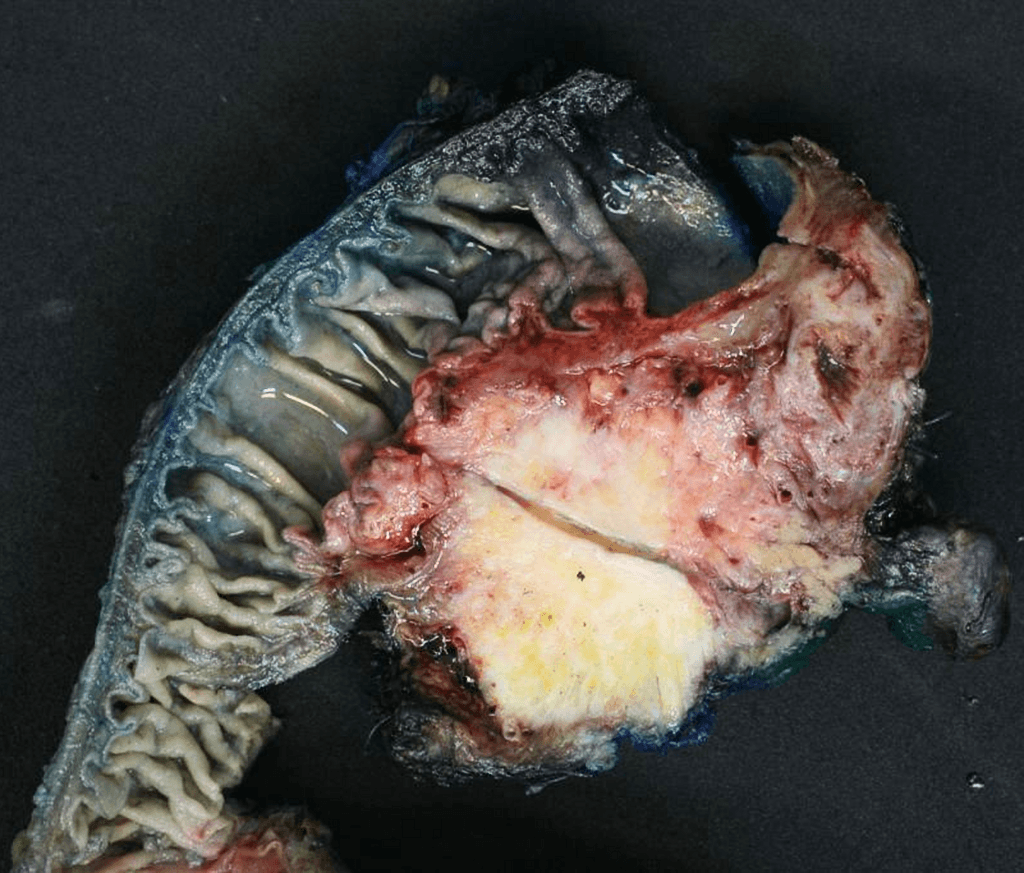

Pancreatic Carcinoma (Gross Pathology) (Ung thư tụy (giải phẫu bệnh đại thể))